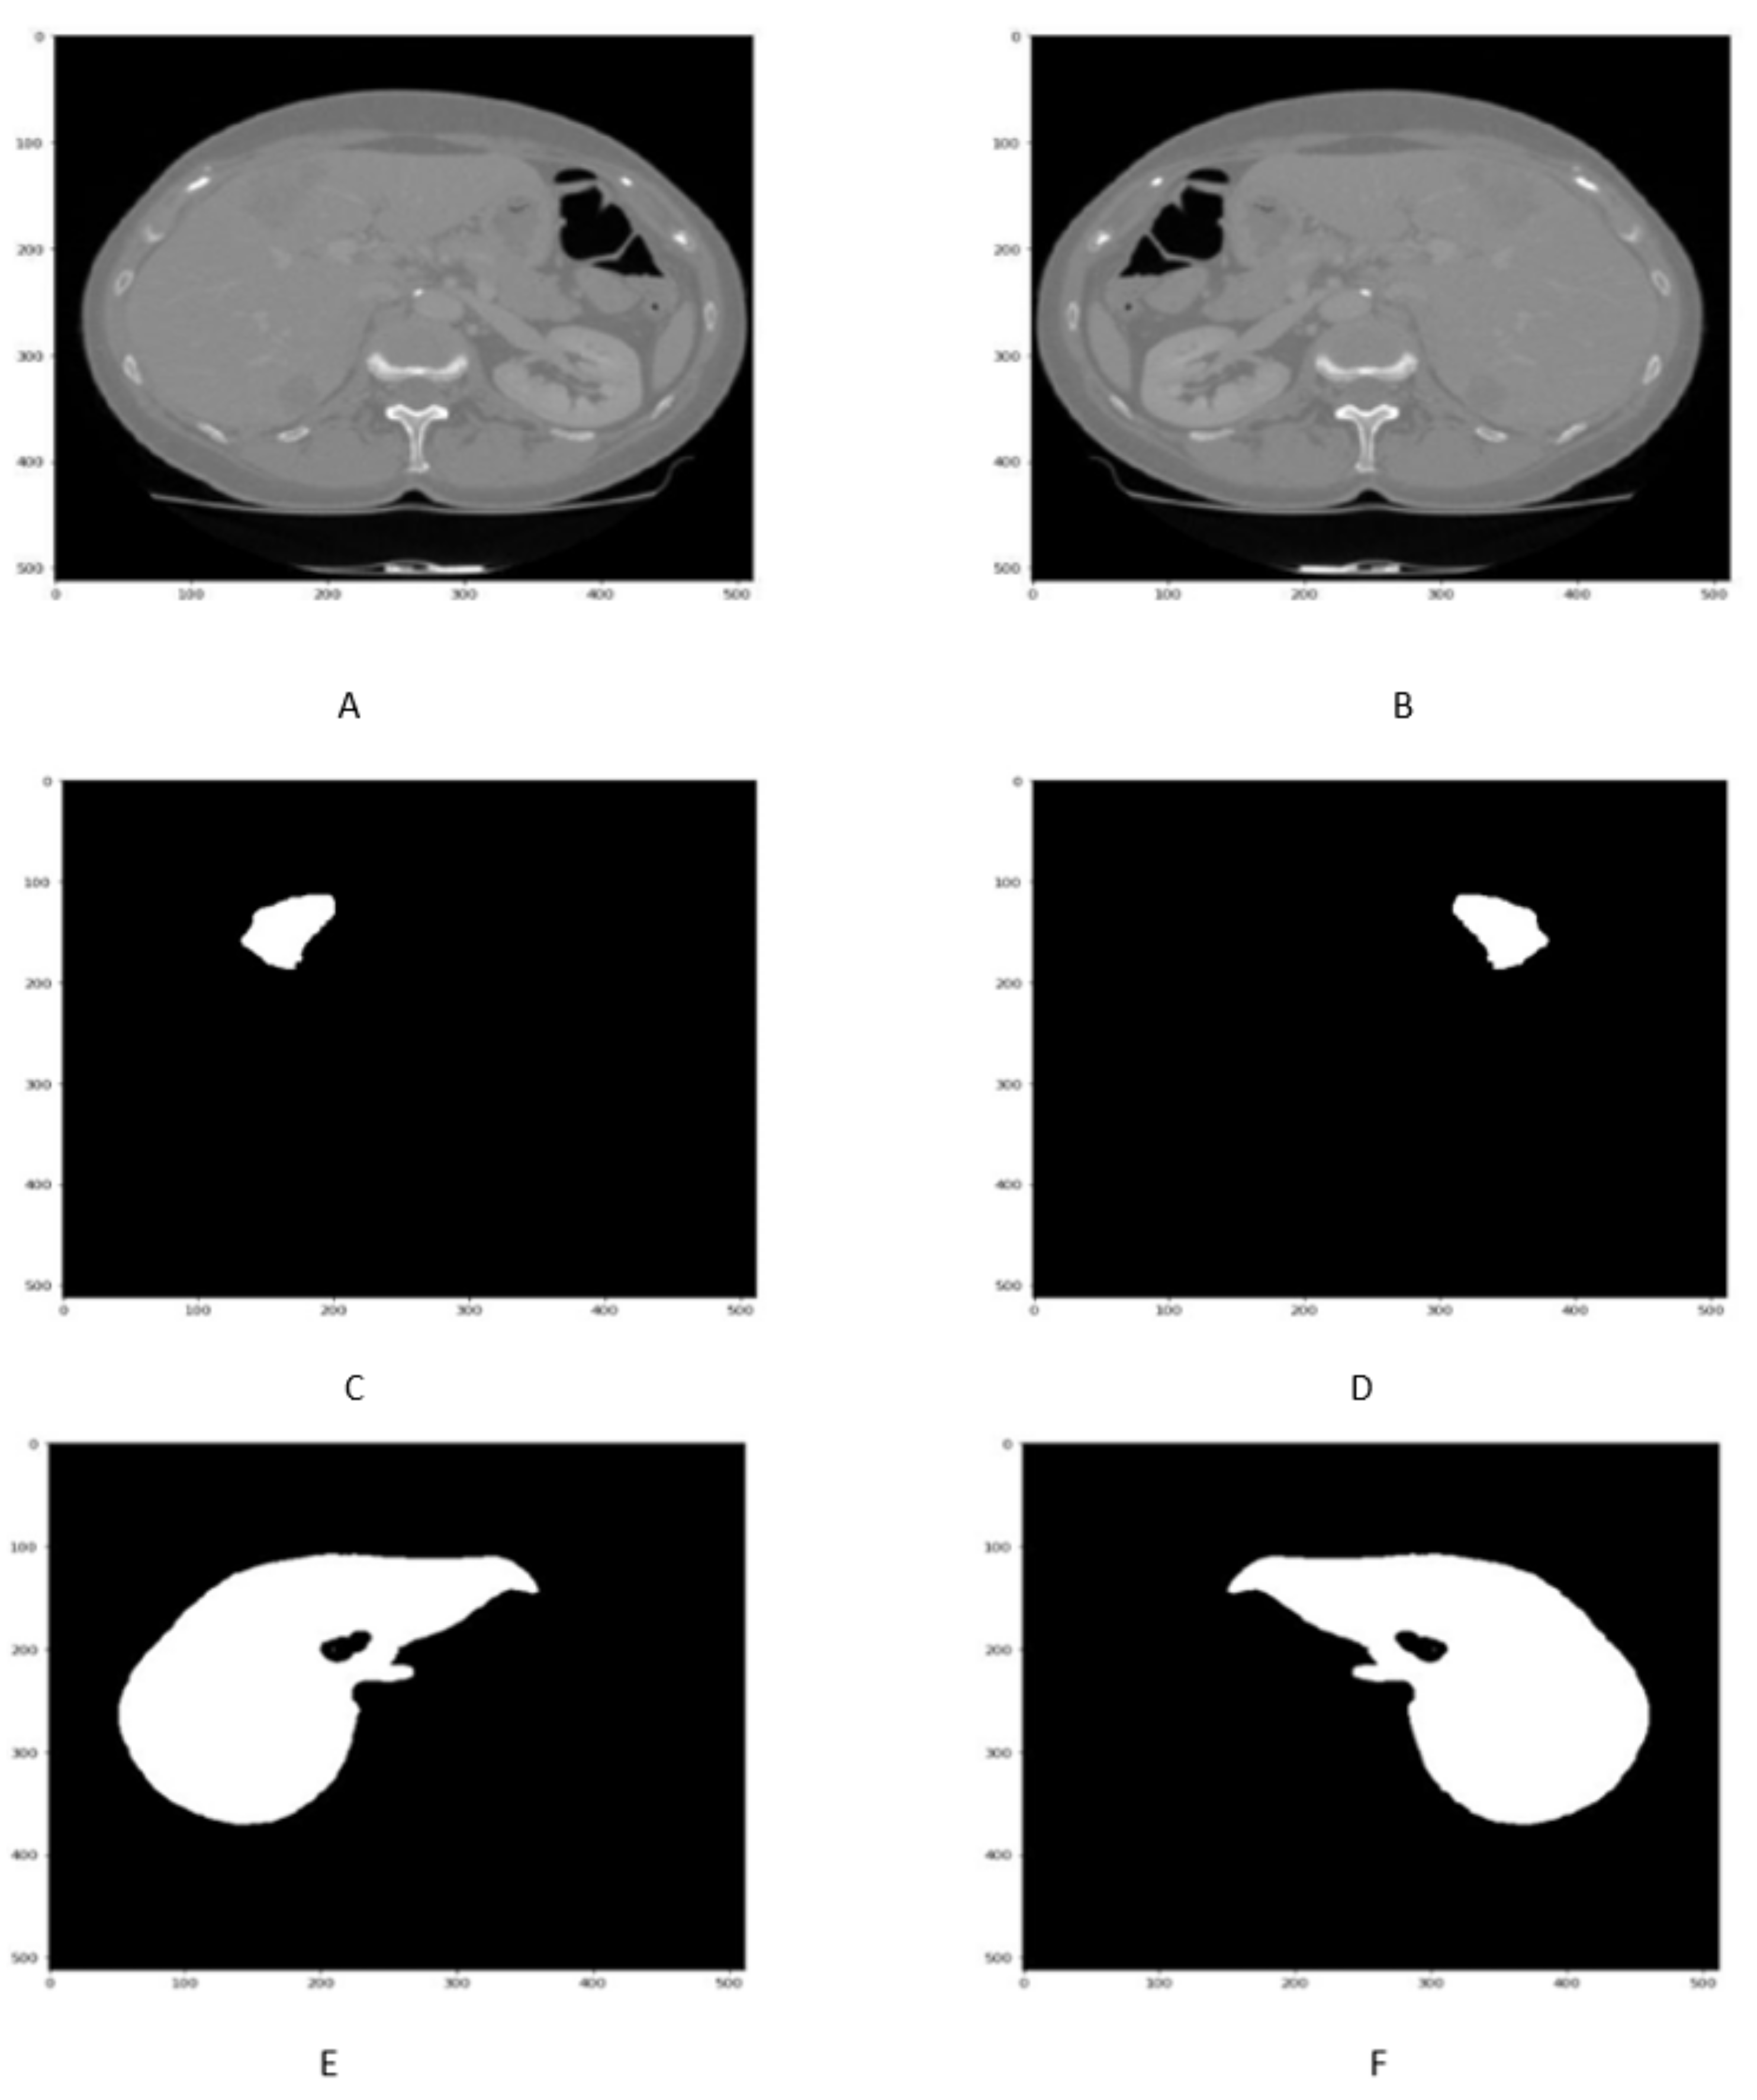

Reflection is a data augmentation technique in which the image can be flipped across the x or y-axis to generate more samples for network training. In order to avoid the computational expense, the liver images along with its tumor masks are reflected as shown in Figure 4A–F.

Figure 4.

Figure shows that the Liver scan tumor mask before 90 in (A,C,E) While liver scan and tumor mask in (B,D,F) after reflection.